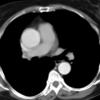

Ao Diss 1c

Date: 01/21/2006

Views: 3694